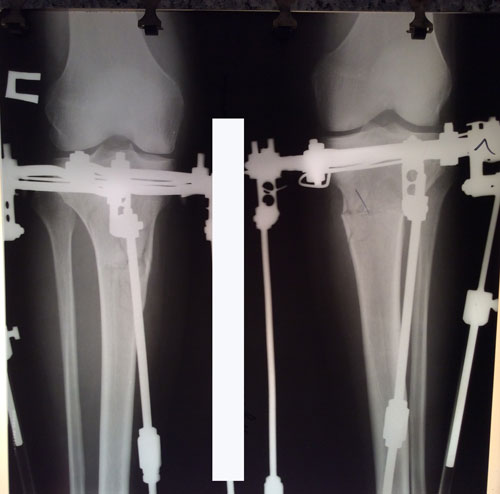

Рентген на фиксации.

IMG_2156-13-02-17-08-48.jpg

IMG_2155-13-02-17-08-48.jpg